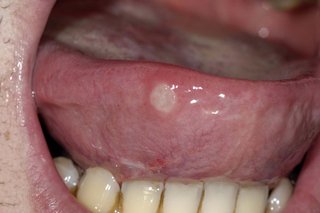

- you have white patches on your tongue

A white tongue can be a sign of a health condition, such as anaemia, scarlet fever, lichen planus, leukoplakia, geographic tongue, mouth ulcers or oral thrush.

Mouth ulcer